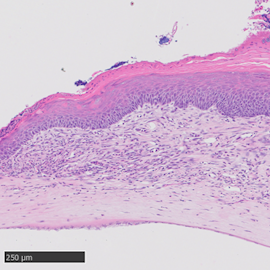

そこで、遺伝子改変技術により、生まれつきペリオスチン遺伝子を持っていないFADSマウスを作成したところ、眼病変(炎症や血管新生など)を発症しないか、眼病変が非常に軽度になりました。このことから、ペリオスチンがFADSマウスの眼病変の重要な原因となっていることが証明されました。

| ペリオスチンを欠損すると眼の炎症が通常のFADSマウスより改善 | |||

この「CP4715」をAKC様の病態を発症したFADSマウスに点眼投与すると(2回/日、14日間)、眼病変が著明に改善することを、今回見出しました。「CP4715」を投与した場合、眼の炎症が改善し、眼の血管新生も改善しました。

| CP4715を投与すると炎症が改善する | |||